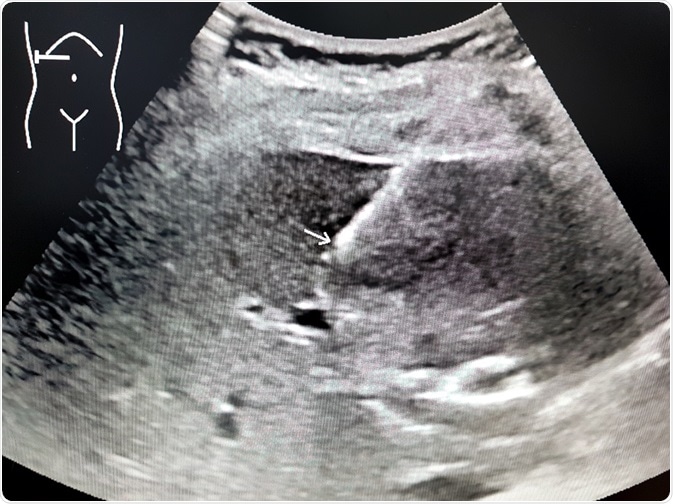

The next step is to use imaging techniques, such as ultrasound and CT scanning of the abdomen, to show the size and the presence of fatty degeneration of the liver. This is not a definitive criterion, however, because false negative results are quite common.

• Ascites or a hyperechoic liver on ultrasound scanning